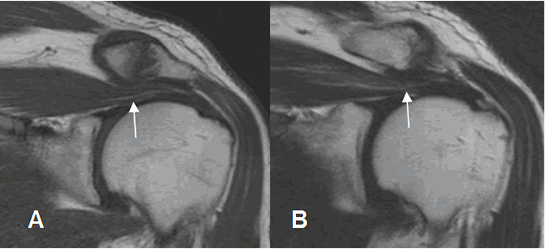

Fig 87. Cambios degenerativos en articulación acromioclavicular.

A: RM coronal en T1 y B: RM coronal en T2. Cambios degenerativos en la articulación acromioclavicular, que comprimen el tendón del supraespinoso. (Flechas).